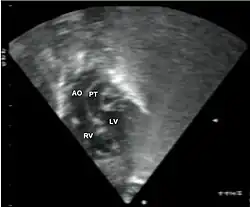

Abbreviations: LV and RV=left and right ventricle, PT=pulmonary trunk, VSD=ventricular septal defect, PS=pulmonary stenosis.